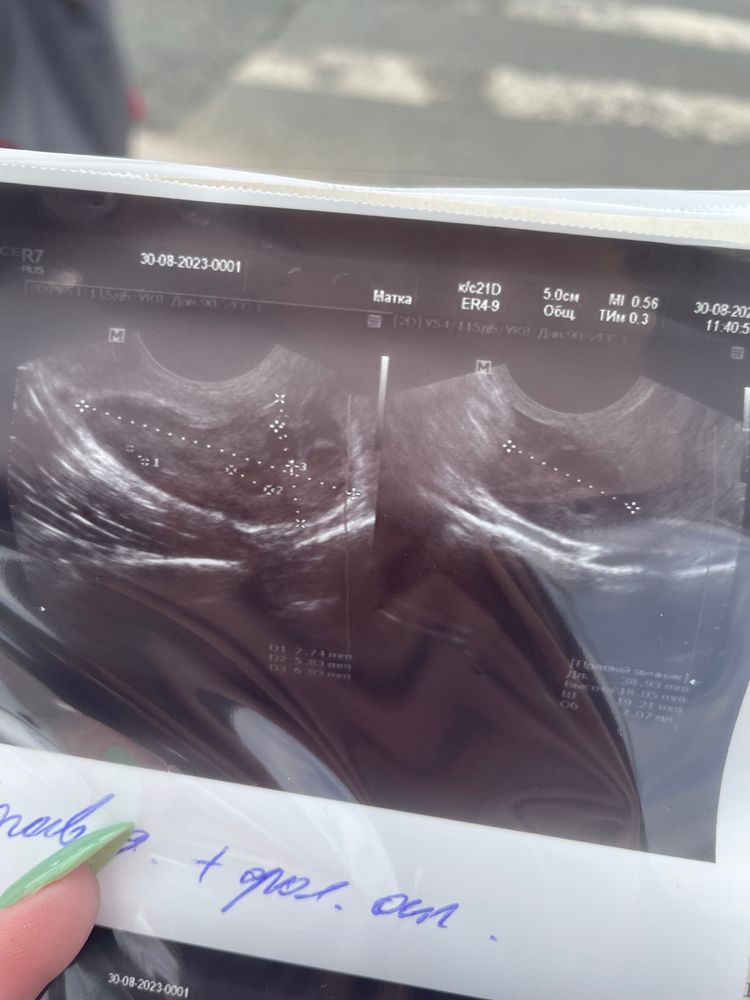

Сегодня была на узи,пришла вообще смотреть наличие опухоли.Узист долго смотрел все органы и выдал данный диагноз. Так еще и заявил,что будут проблемы с родами и впринципе с зачатием. Для подтверждения диагноза сказал сходить на МРТ. Никогда не думала,что в 21 год узнаю об этом. Вопрос в чем состоит,почему мне раньше ,что в 14 лет,что в 17 не говорили об этом и почему только сейчас выявилось ,что матка такая и какая возможность родить ? Как часто выкидыши случались? Снимок узи прикрепляю